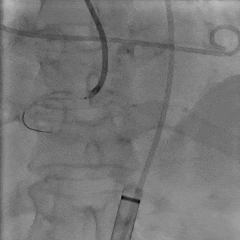

TEE长轴:瓣膜深度可

TEE短轴:瓣膜展开良好,仅少量瓣周漏

-

主瓣峰值流速由术前4.2m/s降至术后1.69m/s

主瓣峰值压差由术前70mmHg降至术后11mmHg